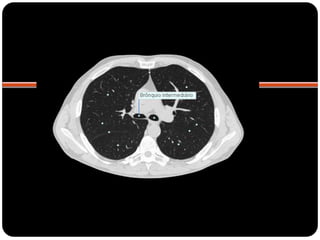

BPD: BLSD

BI - BLM

BI – BLID

BPE: BLSE

BLIE